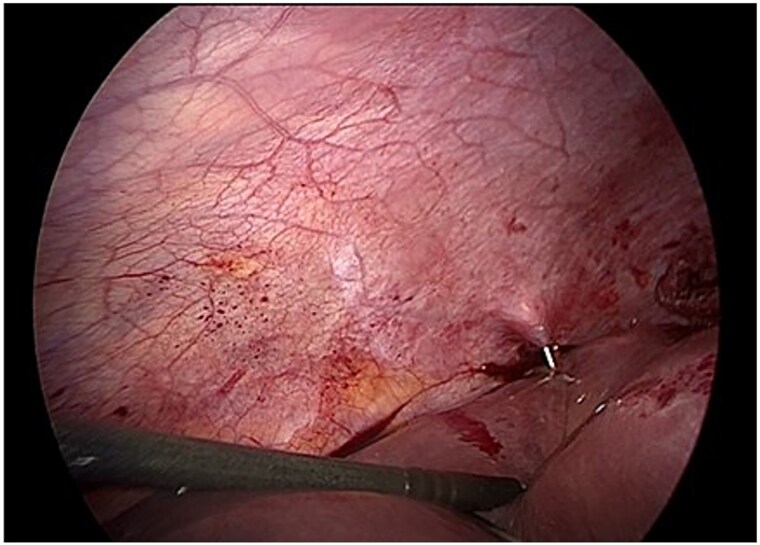

由细粒棘球绦虫引起的肝包虫病在流行地区仍然很流行。手术是治疗的基石,尽管在过去的十年中,腹腔镜方法在选定的病例中获得了突出的地位。我们提出一个病例的加尔比II型肝包虫囊肿成功地通过腹腔镜治疗。19岁男性,来自农村流行地区,表现为右上腹部疼痛。影像学显示肝后段VII有Gharbi 2型包虫囊肿。腹腔镜下对囊肿内容物进行了严格的预防措施,以避免播散。患者预后良好,无并发症。在经验丰富的中心,腹腔镜为没有胆道通信的周围囊肿提供了安全的选择。适当的患者选择和技术熟练程度对于最小化风险至关重要。本报告强调了在精心挑选的患者中腹腔镜治疗Gharbi II型囊肿的可行性,并说明了腹腔镜作为PAIR失败后的抢救策略的作用。

Hepatic hydatidosis, caused by Echinococcus granulosus, remains prevalent in endemic regions. Surgery is the cornerstone of treatment, although laparoscopic approaches have gained prominence in selected cases in the past decade. We present a case of a Gharbi-type II hepatic hydatid cyst successfully treated via laparoscopy. A 19-year-old man from a rural endemic area, presented with right upper quadrant pain. Imaging revealed a Gharbi type 2 hydatid cyst in the posterior segment VII of the liver. Laparoscopic evacuation of the cyst content was performed with strict preventive measures to avoid dissemination. The patient had a favorable outcome without complications. Laparoscopy offers a safe alternative for peripheral cysts without biliary communication and in experienced centers. Proper patient selection and technical proficiency are essential to minimize risks. This report highlights the feasibility of laparoscopic management of Gharbi type II cysts in carefully selected patients and illustrates the role of laparoscopy as a salvage strategy following failed PAIR.